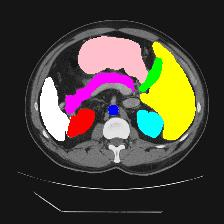

Medical image segmentation is one of the most fundamental tasks concerning medical information analysis. Various solutions have been proposed so far, including many deep learning-based techniques, such as U-Net, FC-DenseNet, etc. However, high-precision medical image segmentation remains a highly challenging task due to the existence of inherent magnification and distortion in medical images as well as the presence of lesions with similar density to normal tissues. In this paper, we propose TFCNs (Transformers for Fully Convolutional denseNets) to tackle the problem by introducing ResLinear-Transformer (RL-Transformer) and Convolutional Linear Attention Block (CLAB) to FC-DenseNet. TFCNs is not only able to utilize more latent information from the CT images for feature extraction, but also can capture and disseminate semantic features and filter non-semantic features more effectively through the CLAB module. Our experimental results show that TFCNs can achieve state-of-the-art performance with dice scores of 83.72\% on the Synapse dataset. In addition, we evaluate the robustness of TFCNs for lesion area effects on the COVID-19 public datasets. The Python code will be made publicly available on https://github.com/HUANGLIZI/TFCNs.

翻译:医学图像分解是医学信息分析的最根本任务之一,到目前为止已经提出了各种解决办法,包括许多深层次的学习技术,如U-Net、FC-DenseNet等。 然而,高精度医学图像分解由于医疗图像中存在固有的放大和扭曲,以及存在与正常组织密度相似的损伤,因此仍是一项极具挑战性的任务。在本文件中,我们建议TFCN(全面革命稠密网络的传输者)通过向FC-DenseNet引进ResLear-Transerferent(R-Transerfor)和Culvacial线性关注区(CLAB)来解决这一问题。TFCN不仅能够利用CT图像中更多的潜在信息来提取特征,而且还能够通过CLAB模块更有效地捕捉和传播语性特征和过滤非神经性特征。我们的实验结果表明,TFCN可以在Syapseion/SymblyDDS上以83CN-72 ⁇ 的分数实现状态。此外,我们在Synapse-DRIS数据设置上,我们还将评估CUTFTFI/LIS的可靠度。